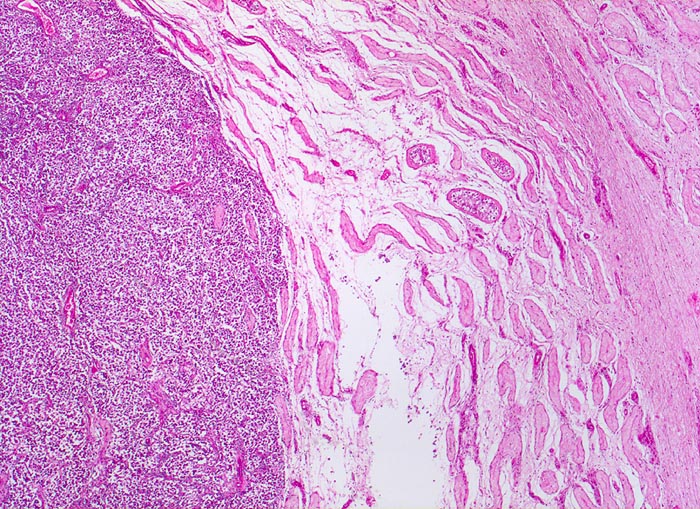

Seminom des Hodens

Links das zellreiche Tumorgewebe mit expansivem, verdrängendem Wachstum. Das angrenzende Hodenparenchym zeigt eine vollständige tubuläre Atrophie ohne erkennbare Spermatogenese. Vereinzelte Tubuli enthalten atypische Zellen.

Makroskopisch aus mehreren Knoten bestehender weisser Tumor von 2cm Durchmesser.

Der Patient suchte den Arzt wegen einer schmerzlosen Hodenvergrösserung auf.